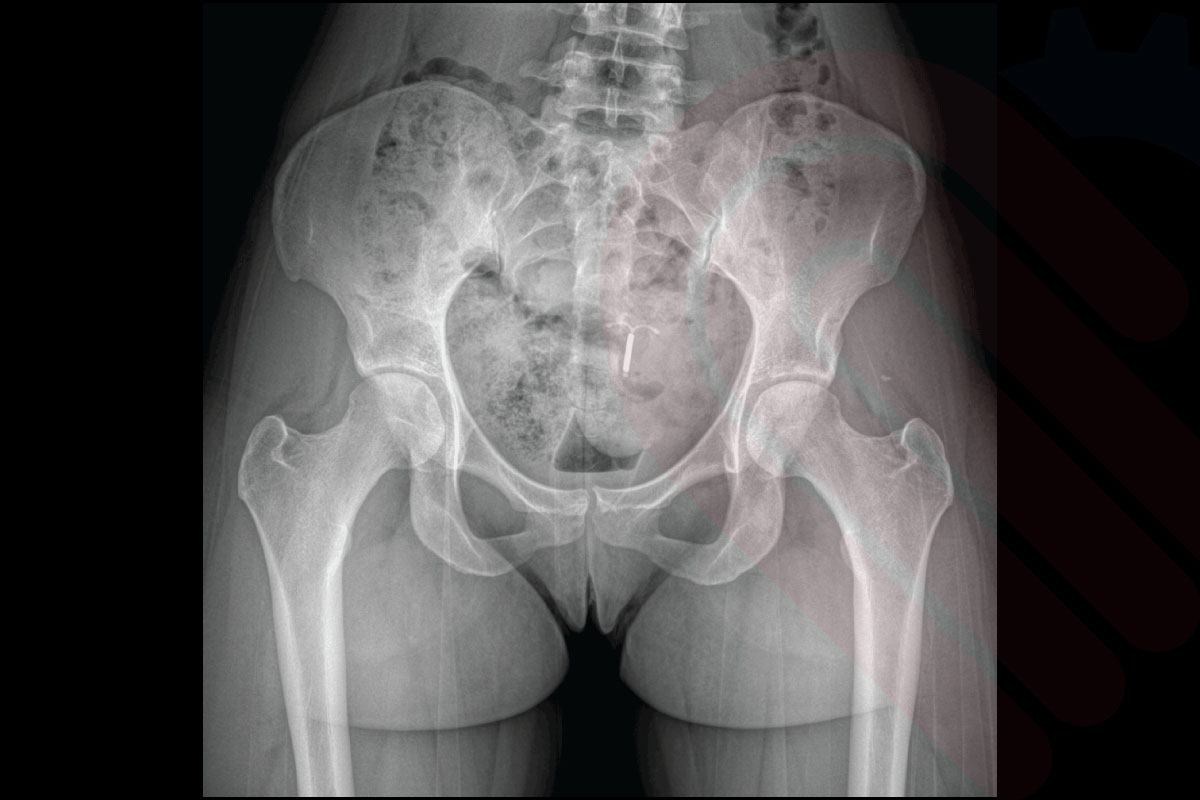

hipEOS, EOSedge sistemi ile elde edilen düşük doz, gerçek boyutlu biplanar görüntüler üzerinden kalça ekleminin 3D analizini ve cerrahi planlamasını yapan gelişmiş bir yazılımdır. Total kalça protezi (THA) ve diğer kalça rekonstrüksiyon cerrahilerinde, asetabular kupa açısı, femoral stem pozisyonu, bacak uzunluğu farkı ve offset gibi kritik parametreleri preoperatif olarak belirlemenize olanak tanır. Yük taşıyan pozisyonda elde edilen görüntüler sayesinde, implant yerleşimi ve pozisyonlaması hastanın doğal biyomekaniğine en uygun şekilde planlanabilir. Klinik veriler, hipEOS planlaması ile gerçekleştirilen operasyonlarda postoperatif bacak uzunluğu eşitliği ve komponent pozisyon doğruluğunda anlamlı iyileşmeler olduğunu göstermektedir*.

Klinik Destek

• Sariali et al., Clinical Orthopaedics and Related Research, 2012

→ hipEOS planlaması ile yapılan THA cerrahilerinde asetabular komponent yerleşim doğruluğu ve bacak uzunluğu eşitliği anlamlı düzeyde artmıştır.